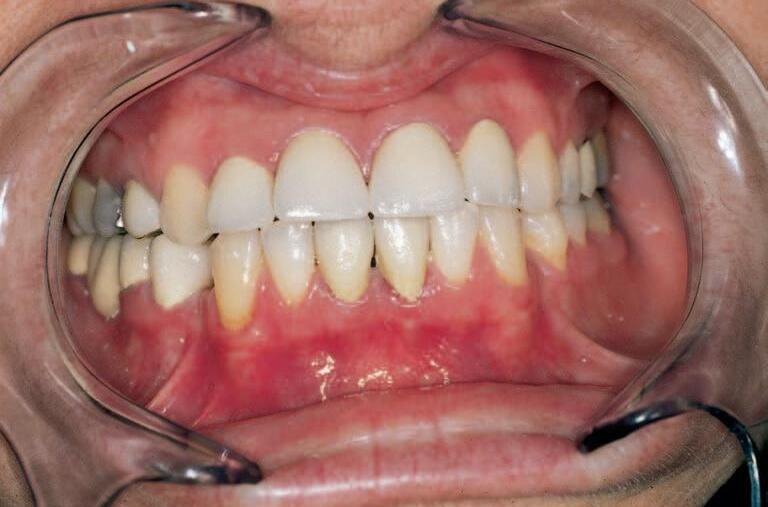

Simulacebudoucíproteticképráce(obr.10,11)pacientoviijehonejbližšímpomùžerozhodnout,zdajeoptimálníprovéstnavrhovanourekonstrukci(obr.12)avjakémrozsahu(obr.13).

Analýzamodelùvartikulátoruspoluspøenosemanatomickýchrozmìrùsindividuálnímnastavenímsklonukloubníchdrahdovolíoptimálnìtvarovatokluzníhopole (obr.10,13).

Obr.13 Estetickývzhledpacientaporekonstrukci